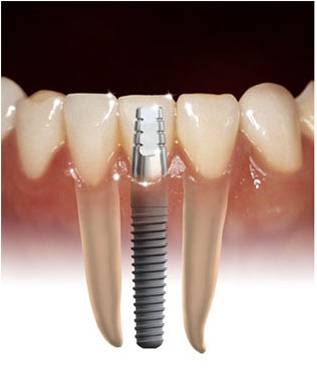

Implantes dentales

Los implantes dentales se utilizan para reponer las piezas dentarias faltantes, debido a sus caracteristicas "se sienten como los originales".